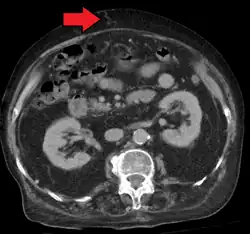

Portal hypertension due to cirrhosis resulting in revascularization of the umbilical vein

Ultrasonography (US) is the first-line imaging technique for the diagnosis and follow-up of portal hypertension because it is non-invasive, low-cost and can be performed on-site.[17]

A dilated portal vein (diameter of greater than 13 or 15 mm) is a sign of portal hypertension, with a sensitivity estimated at 12.5% or 40%.[18] On Doppler ultrasonography, a slow velocity of <16 cm/s in addition to dilatation in the main portal vein are diagnostic of portal hypertension.[19] Other signs of portal hypertension on ultrasound include a portal flow mean velocity of less than 12 cm/s, porto–systemic collateral veins (patent paraumbilical vein, spleno–renal collaterals and dilated left and short gastric veins), splenomegaly and signs of cirrhosis (including nodularity of the liver surface).[17]